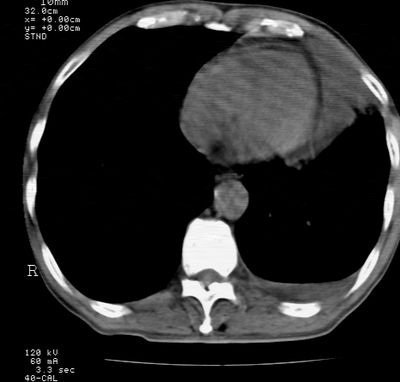

标题: CT24000:M65,胸痛,胸闷月余,既往慢支,肺气肿,肺心病 [打印本页]

标题: CT24000:M65,胸痛,胸闷月余,既往慢支,肺气肿,肺心病

1左侧胸腔积液

左肺门见巨大软组织肿块影,直径约--,境界清,左上肺叶支气管变窄,左上肺舌叶见大片状密实影,余肺纹理增多、紊乱、纤细、部分网格状,两肺透亮度增高,纵隔内见增大多发淋巴结影,心影略左偏,左侧少量胸腔积液。

左侧中央型肺癌伴左上肺舌叶不张、纵隔淋巴结转移,左侧少量胸腔积液。